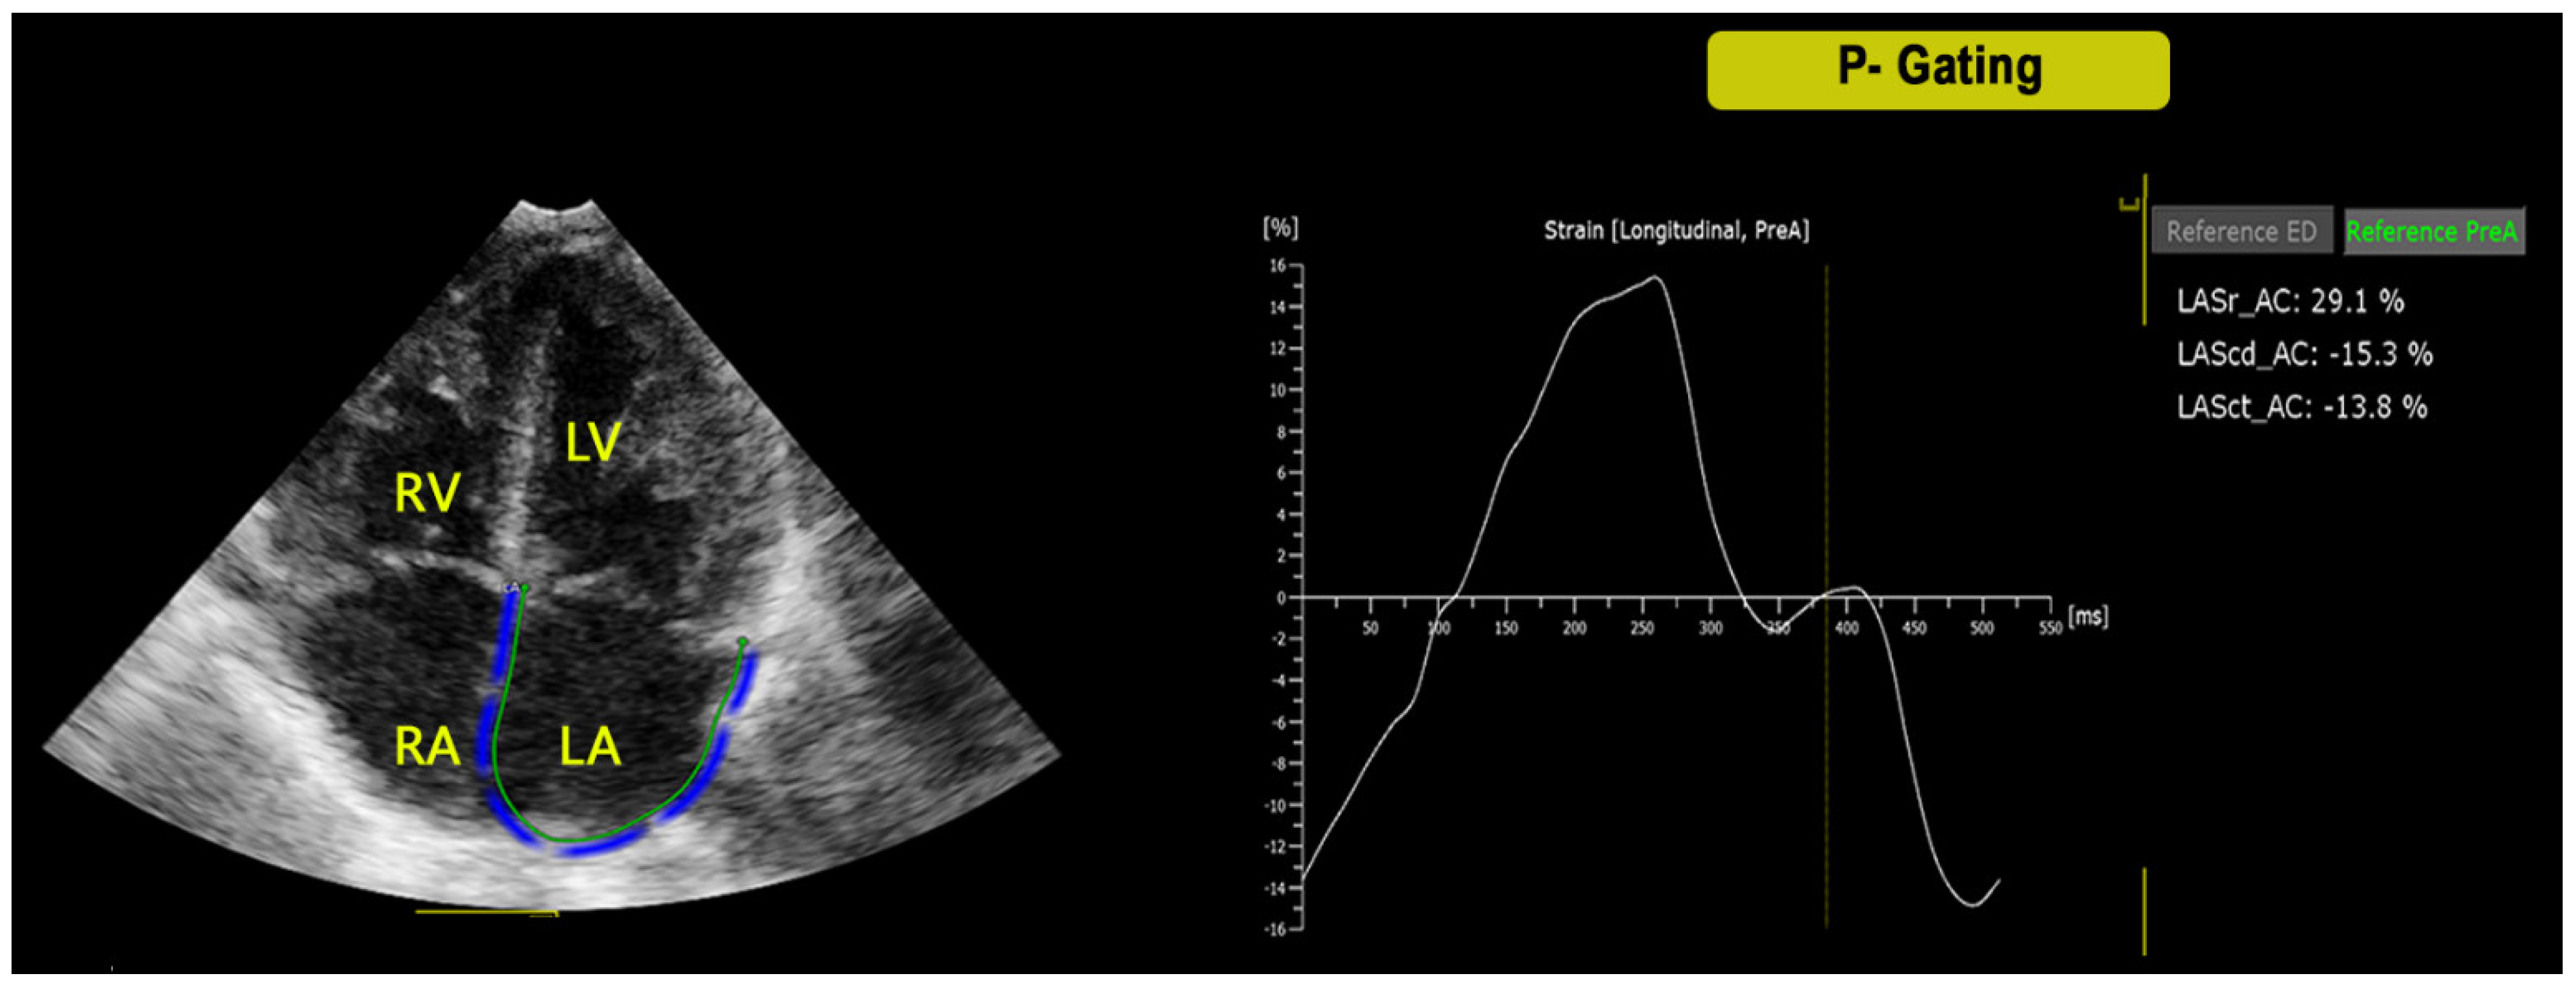

3.6. Differences among P- and R-Gating Post-Operative ε Values

- Marchese, P.; Scalese, M.; Giordano, R.; Assanta, N.; Franchi, E.; Koestenberger, M.; Ravaglioli, A.; Kutty, S.; Cantinotti, M. Pediatric ranges of normality for 2D speckle-tracking echocardiography atrial strain: Differences between p- and r-gating and among new (Atrial Designed) and conventional (Ventricular Specific) software’s. Echocardiography 2021, 38, 2025–2031. [Google Scholar] [CrossRef] [PubMed]

| (P-Gating) LA ε R | 45.19 ± 13.03 | 30.72 ± 9.34 | 22.69 ± 9.62 | 26.46 ± 8.58 | 30.58 ± 10.21 |

| (P-Gating) LA ε Cd | 33.25 ± 12.57 | 18.37 ± 8.87 | 14.7 ± 7.92 | 16.41 ± 7.3 | 19.05 ± 7.82 |

| (P-Gating) LA ε Ct | 12.6 ± 5.41 | 12.36 ± 4.89 | 9.36 ± 5.89 | 10.61 ± 5.65 | 11.68 ± 6.45 |

| (P-Gating) RA ε R | 40.7 ± 13.15 | 33.22 ± 9.48 | 17,23 ± 7.92 | 20.26 ± 6.93 | 24.56 ± 11.13 |

| (P-Gating) RA ε Cd | 27.04 ± 12.4 | 19.9 ± 7.98 | 10.35 ± 6.55 | 12.64 ± 8.2 | 14.86 ± 9.22 |

| (P-Gating) RA ε Ct | 14.31 ± 6.52 | 13.38 ± 5.8 | 8.15 ± 5.72 | 8.98 ± 5.41 | 10.59 ± 5.8 |